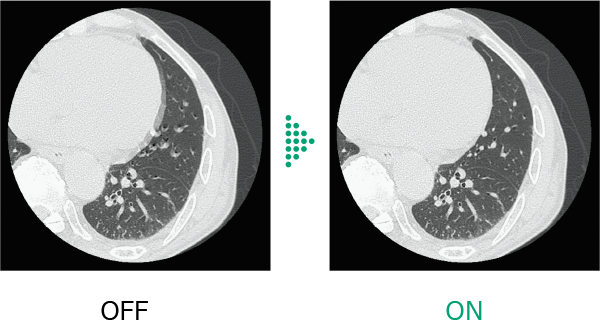

Conventional chest CT scans*1 have faced challenges due to motion artifacts caused by heartbeat and patient motion , making diagnosis difficult in some cases.

Body StillShot*2 calculates the direction and amount of patient motion in four dimensions from the collected raw data, providing images with minimal blurring caused by motion . It can also be used in combination with Intelli IPV*3 , an image reconstruction technology developed using AI, contributing to further image quality improvement.